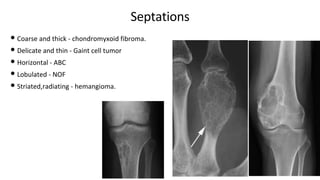

Septations

• Coarse and thick - chondromyxoid fibroma.

• Delicate and thin - Gaint cell tumor

• Horizontal - ABC

• Lobulated - NOF

• Striated,radiating - hemangioma.